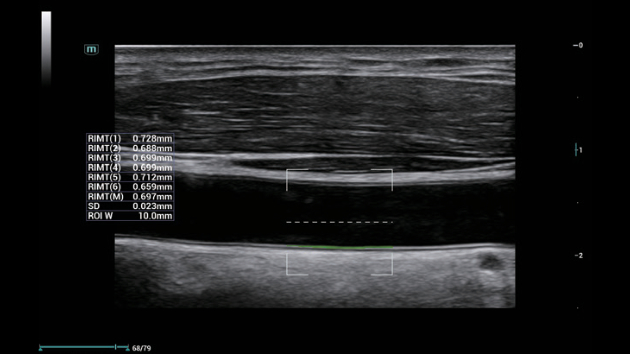

ZST+ ??? ???? ?? ???

ZST+ ???? ???? ??? ???? ??? ?????. ??? ???? ?? ? ???? ?? ??? ?? ??? ?????. ??? ??? ? ?? ??? ??? ???? ?????? ??? ???? ???? ??? ?? ?? ?? ?? ???? ?? ??? ?? ??? ?????.